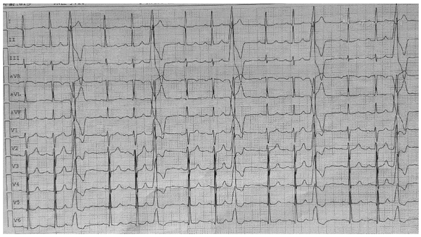

辅助检查:入院动态心电图提示频发室性早搏35 889次/24h,室早负荷30%。超声心动图示无明显异常。肝功能、肾功能、电解质及甲状腺功能均正常。术前心电图特点,V1导联呈Rs型,胸前导联全部正向,移行较早,Ⅱ、Ⅲ、avF导联呈高大的R波,Ⅰ导联负向,RⅢ>RⅡ,考虑室性早搏来源于左室流出道左冠窦(Summit区域),见图1。